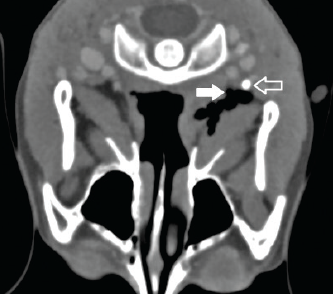

Figure: Axial view of contrast maxillofacial CT obtained approximately 15 hours after a penetrating soft palate injury. The solid arrow indicates tissue dissection, and the outlined arrow marks the right internal carotid artery.

The results of the CT scan were significant only for the known posterior soft tissue laceration. No vascular injury had been sustained, despite the radiologist’s observation that the penetrating laceration had progressed to within 1 mm of the internal carotid artery. The patient was able to resume oral intake and later was discharged home with antibiotic prophylaxis.